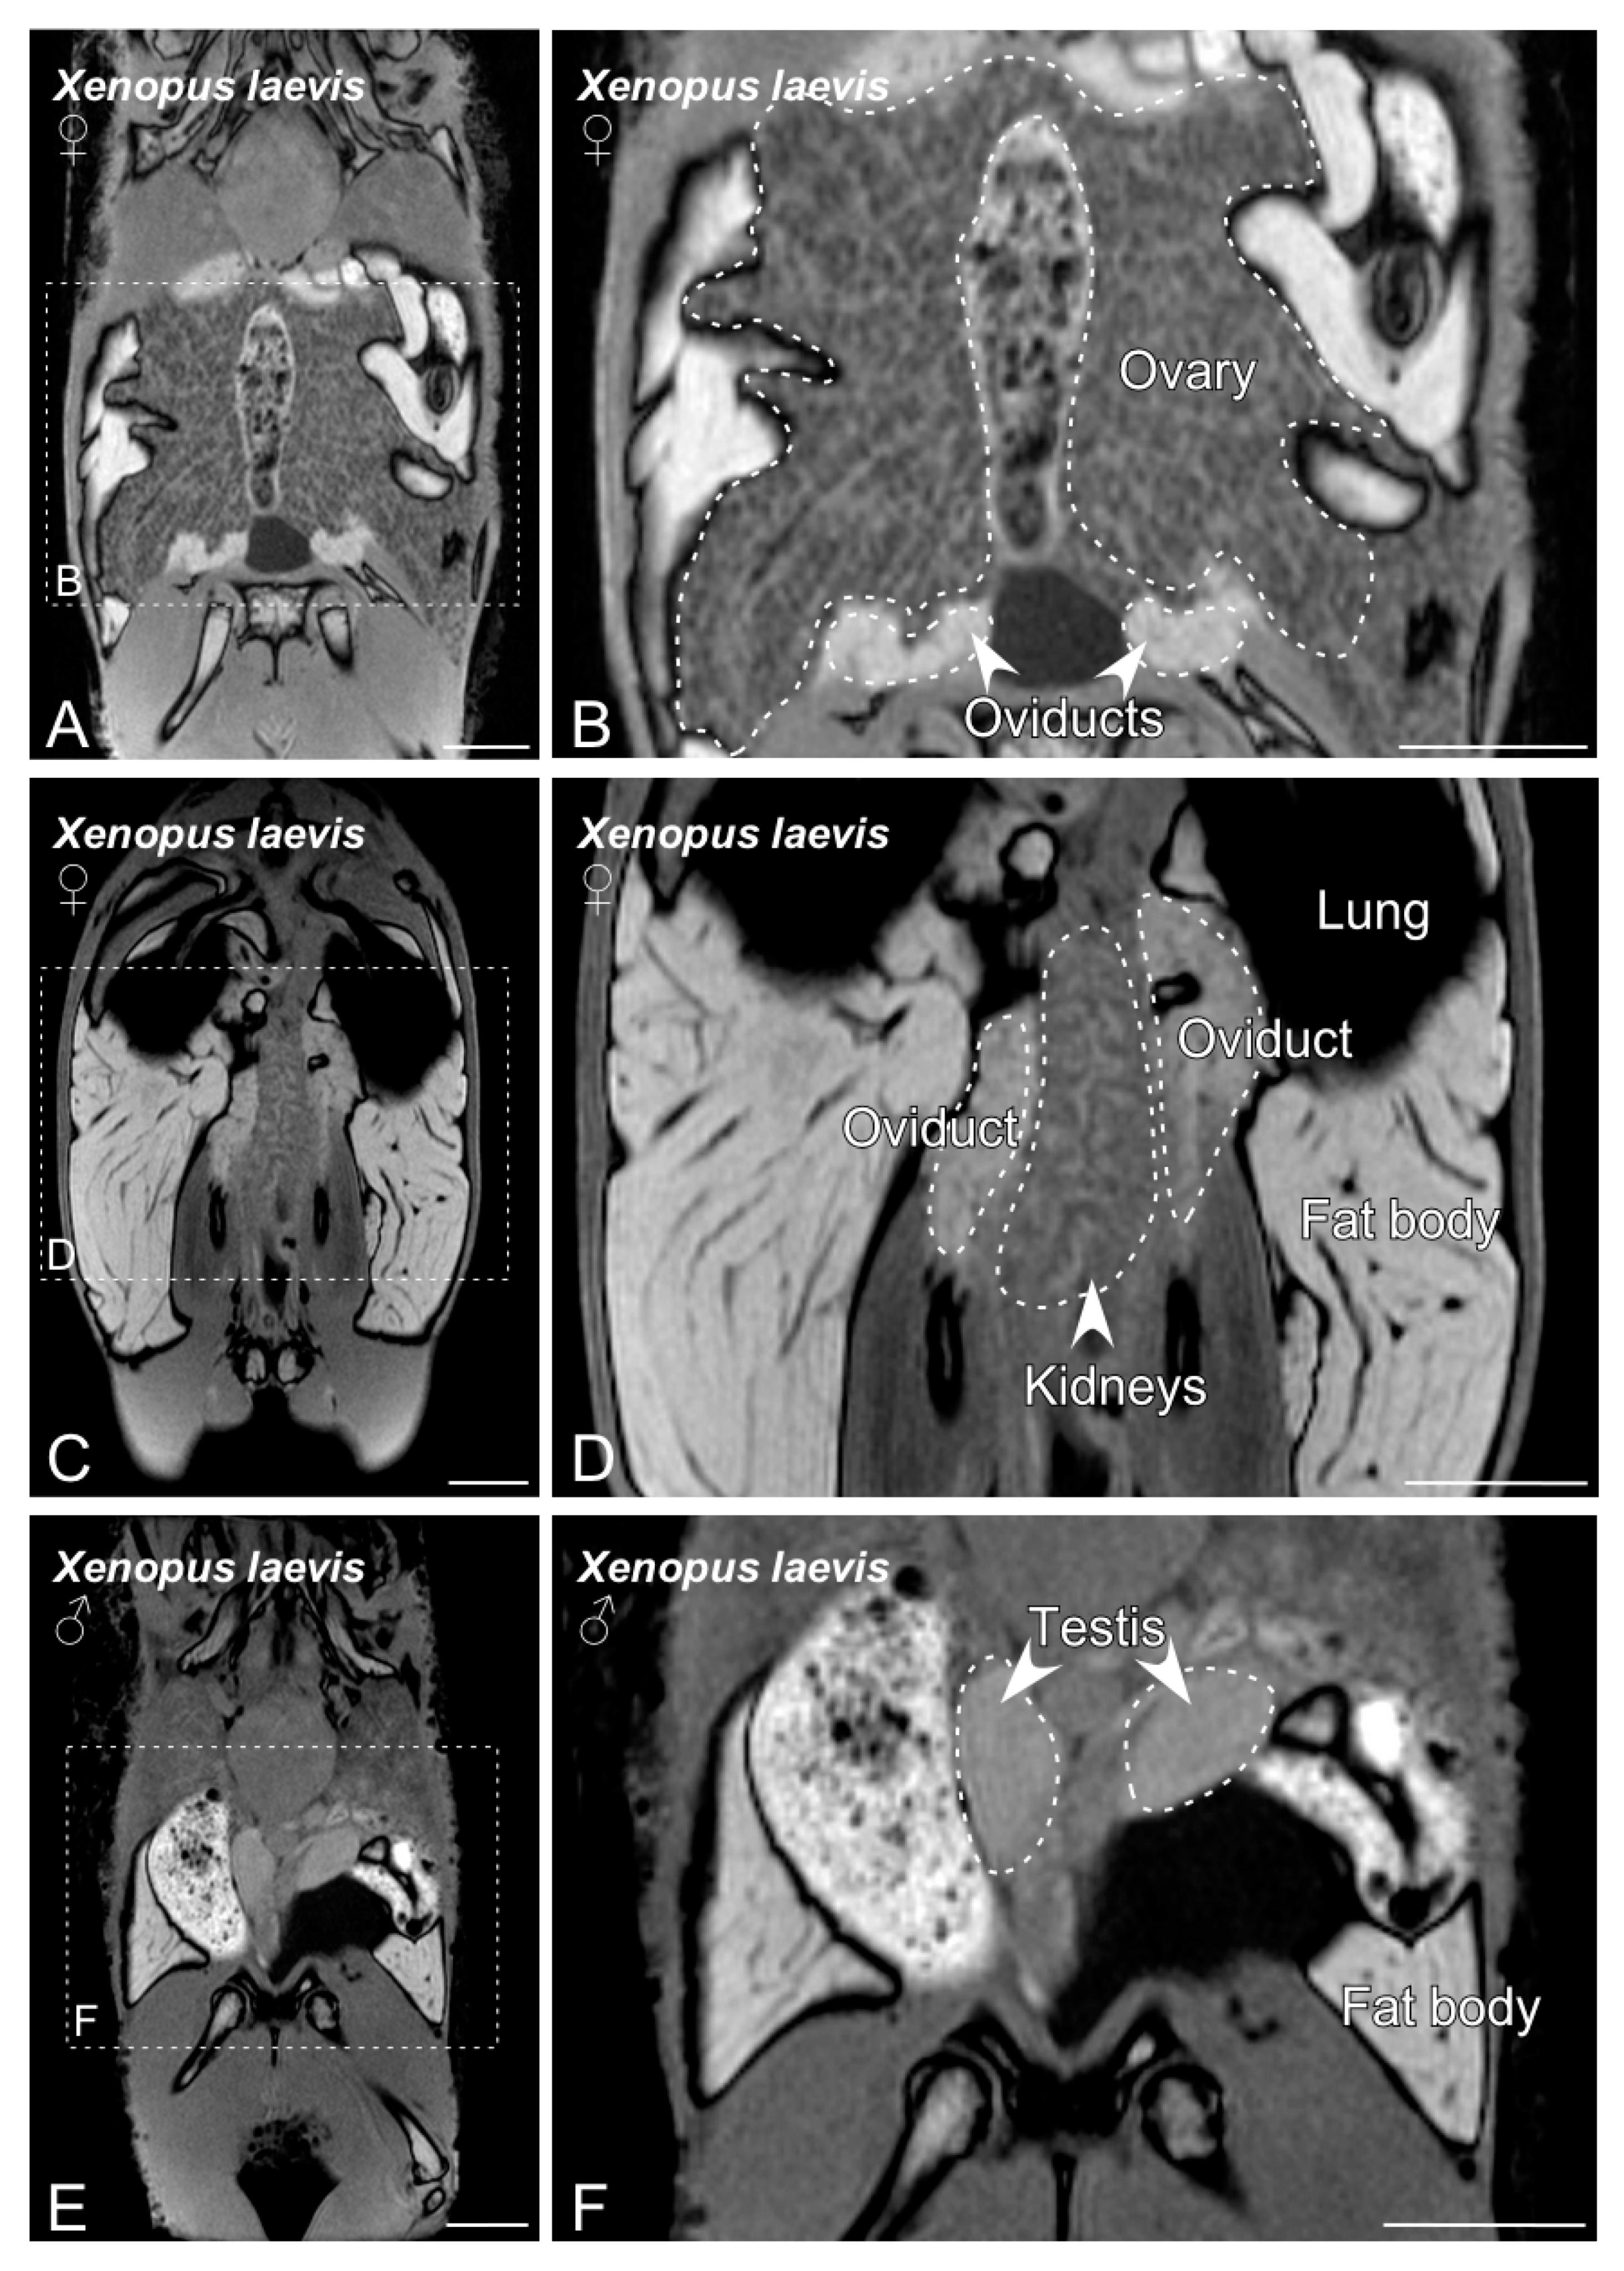

Figure 3. MRI slices selected to illustrate the main sex organs of the Xenopus laevis anurans. Images from (A) to (D) show the structures identified in a gravid Xenopus laevis female. Images (E,F) show testis and fat body in a Xenopus laevis male. The dashed lines in (A,C,E) indicate the magnification photos showed in (B,D,F). Scale bars = 1 cm.